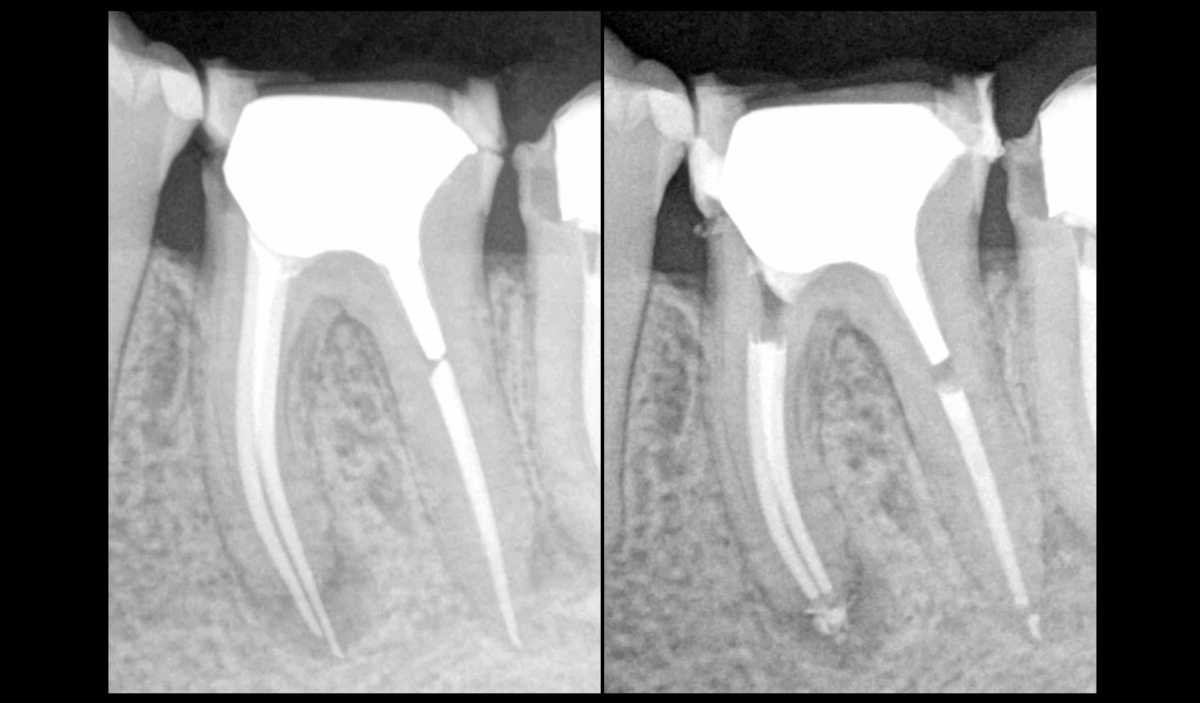

❓ Quel protocole pour désobturer ce dépassement de gutta ?

📌 𝐃𝐚𝐧𝐬 𝐜𝐞 𝐜𝐚𝐬 :

🖐️ Désobturation manuelle

📏 Obtention de la LT

⚙️ Instrumentation mécanisée :

• Race 10.04 (pas EVO)

• 15.04 (EVO)

• 25.04 (EVO)

• XP Shaper